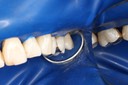

Wayne Chin #14 pre-op